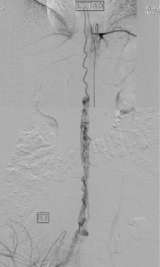

Figure 1: Spinal AVM

Spinal vascular malformation is a very rare condition. It is an abnormal tangle of blood vessels on, in, and/or near the spinal cord (Figure 1).

Depending on where a malformation is located, it is classified as:an intramedullary arteriovenous malformation (AVM within the spinal cord tissue), a pial arteriovenous malformation (AVM on the surface), a dural spinal arteriovenous fistula (DAVF within the membrane that covers the spinal cord), or an epidural arteriovenous fistula (Epidural AVF on the surface of the membrane that covers the spinal cord).

Intramedullary and pial AVMs are considered to be congenital conditions (Figure 1). Larger malformations tend to cause symptoms in a younger age group than smaller AVMs. In fact, smaller malformations can be completely silent. Symptoms from spinal AVMs can occur in a gradual fashion or acutely and dramatically. The symptoms include abnormal sensation in the body, back pain, weakness in the extremities, sexual dysfunction, and bowel/bladder disturbances.